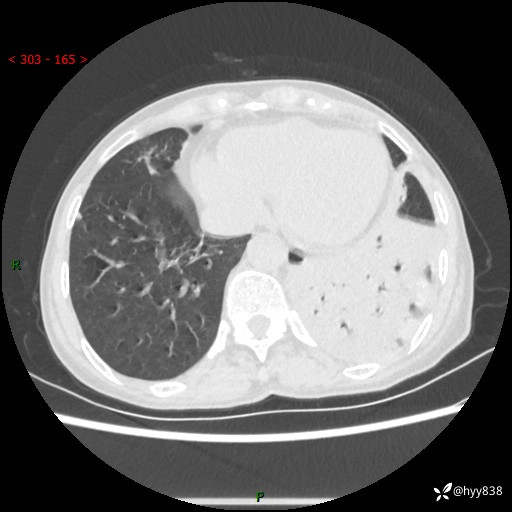

胸部CT平扫+增强